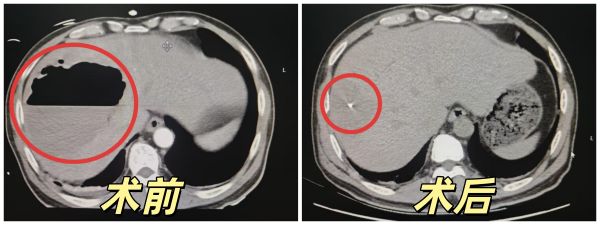

术后,患者转入重症医学科接受进一步观察治疗,次日转回普通病房。通过引流管持续排脓,引流袋中的脓液从最初的“巧克力酱”逐渐变为“清茶水”。复查CT显示,原本12厘米的脓肿已缩小至5厘米,各项感染指标恢复正常。